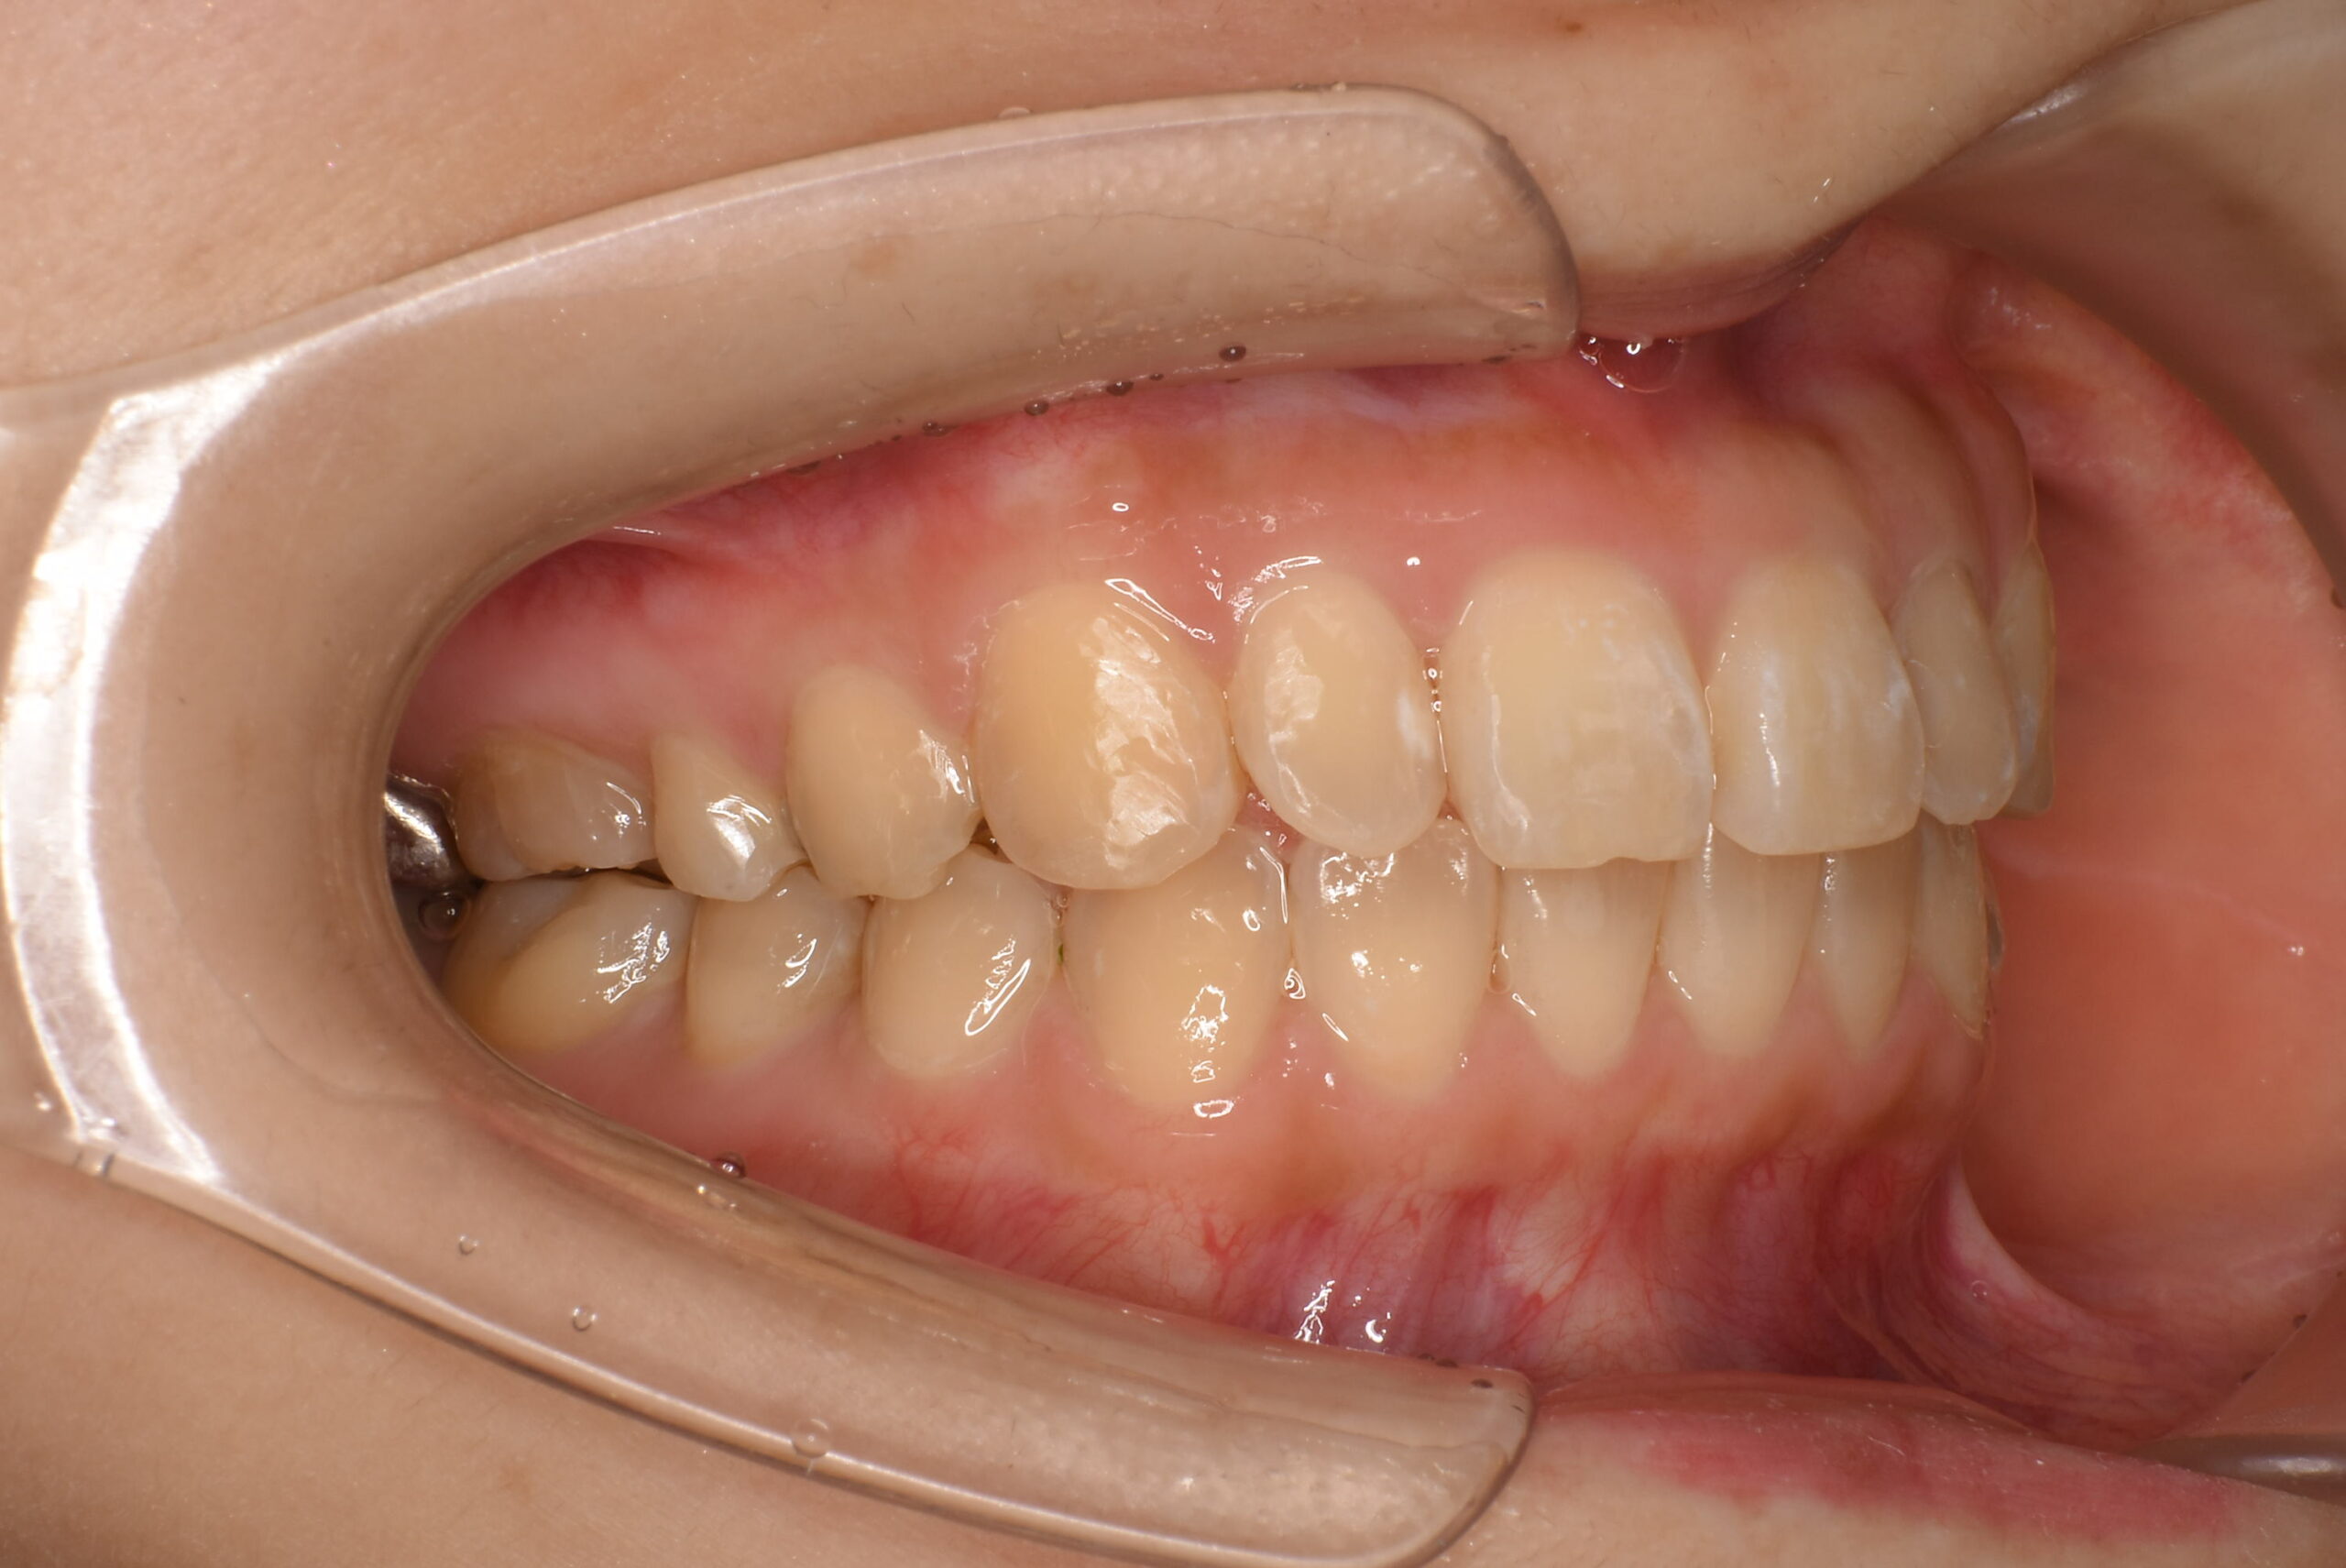

治療後_右側方

| 治療内容 | 不揃いな歯並び(叢生)や、歯のガタガタ・デコボコが気になることを主訴に来院されました。 目立ちにくい装置での治療をご希望されたため、マウスピース型矯正(インビザライン)による矯正治療を行いました。 治療途中、上顎左右にカリエスが認められたため、矯正治療と並行してCR修復(コンポジットレジンによる虫歯治療)を行いました。 2021年12月にお引っ越しのご予定があり、2022年3月までの治療終了を希望されていたため、治療計画を調整しながら進行管理を行い、予定期間内での治療完了を目指しました。 |

| 治療期間/通院回数 | 14ヶ月 |